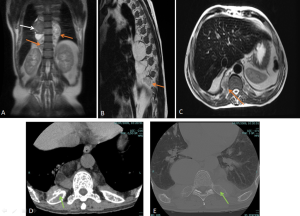

ERDHEIM-CHESTER DISEASE (ECD)

ECD is a rare non-Langerhans cell histiocytosis affecting multiple organ systems, typically presenting in adults in their 5th–7th decades with slight male predominance.

Diagnosis relies on biopsy supported by characteristic clinical and imaging features.

Retroperitoneal and renal involvement occurs in a significant proportion, with CT and MRI demonstrating bilateral perinephric and posterior pararenal soft-tissue infiltration, producing the classic “hairy kidney” appearance. Infiltrates are generally isoattenuating or iso- to hypointense to skeletal muscle with mild contrast enhancement; FDG uptake may be present but can be obscured by physiological renal activity. Chronic infiltration may result in renal atrophy.

Although both ECD and retroperitoneal fibrosis can lead to hydronephrosis, their distribution differs: ECD typically affects the perinephric fat and renal hila, whereas idiopathic RPF encases the anterolateral aorta and proximal ureters. Aortic encasement (“floating aorta sign”) and periureteric involvement may occur, but ECD usually spares the IVC and pelvic ureters. Additional distinguishing features include irregular perirenal infiltration and bilateral symmetric adrenal thickening.

Skeletal involvement, particularly of the femur, tibia and fibula, is seen in most patients, often causing bone pain [9].